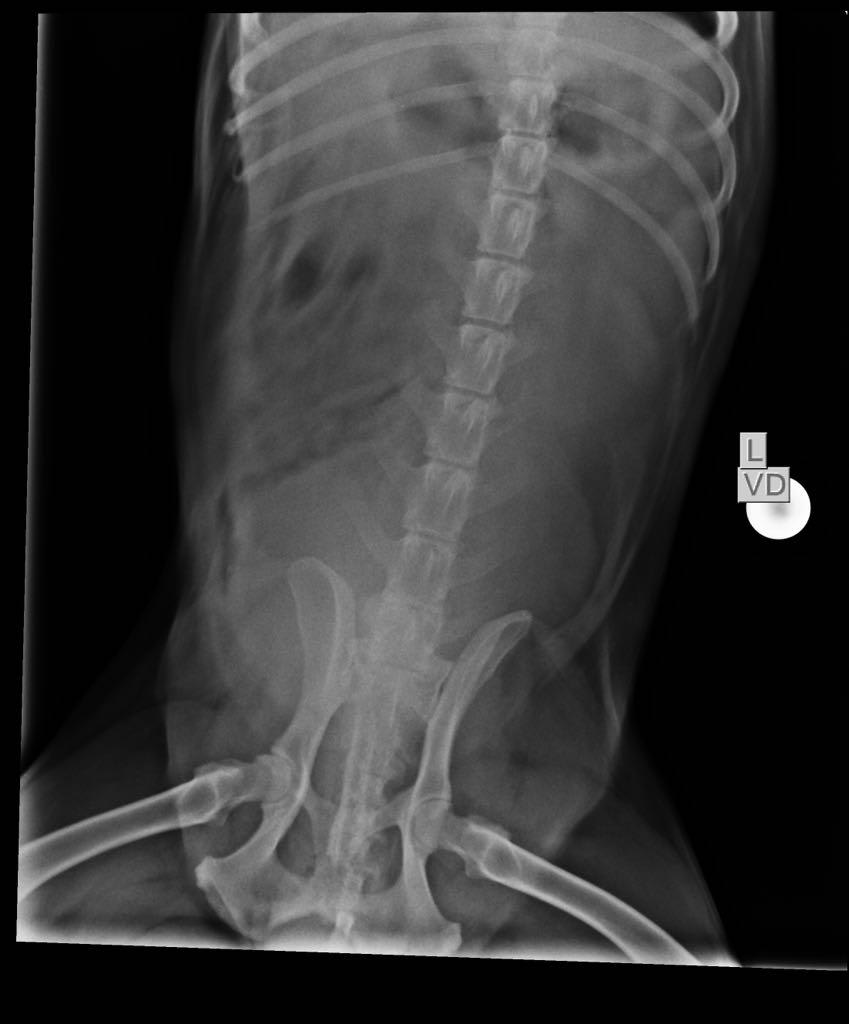

Pet's info: Dog | Mixed Breed | Male | unneutered | 15 years old | 46.5 lbs

Hi, I have a 15year old indie mix breed dog, not neutered been diagnosed with mass in prostrate, biopsy not done. His symptoms limping with hind limb, straining while urinating and passing stool In constant pain around prostate mass and hip bones Vet suggested it’s a 80*88mm tumor and can’t be treated due to surgery so should be put to sleep Please advise as there is no blood in urine and no weight loss yet is there a possibility of that this isn’t tumor and just a mass